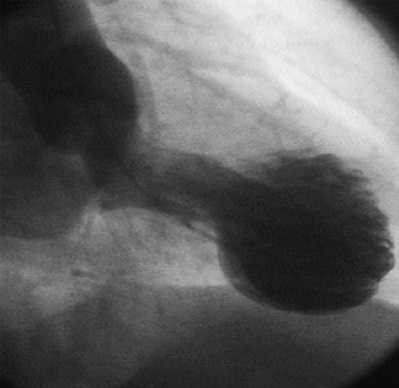

ПРАВАЯ КОРОНАРНАЯ АРТЕРИЯ- окклюзирована в п/3, постокклюзионный сегмент не визуализируется (тромбоз).

ЗБВ ПКА - постокклюзионный сегмент не визуализируется.

ЗМЖВ ПКА - постокклюзионный сегмент не визуализируется.

Тип кровоснабжения - правый.

Ход операции:

Под местной анестезией sol. Lidocaini 2% - 5,0 пунктирована правая лучевая артерия. В/а введено 10 тыс. ед. гепарина.Проводниковый катетер 6F проведен в восходящий отдел аорты и установлен в устье правой коронарной артерии. Выполнена проводниковая реканализация, затем тромбаспирация. Извлечены фрагменты тромба. При контрольной коронарографии выявлен критический стеноз 90-95% с фрагментами пристеночных тромбов. Далее после предварительной дилатации баллонным катетером 2,0х20 мм (12 атм) выполнено стентирование ПКА. Имплантированы стенты "Resolute" 3,5х30 мм (14 атм), "Resolute" 3,0х26 мм (14 атм). Получен хороший ангиографический результат.